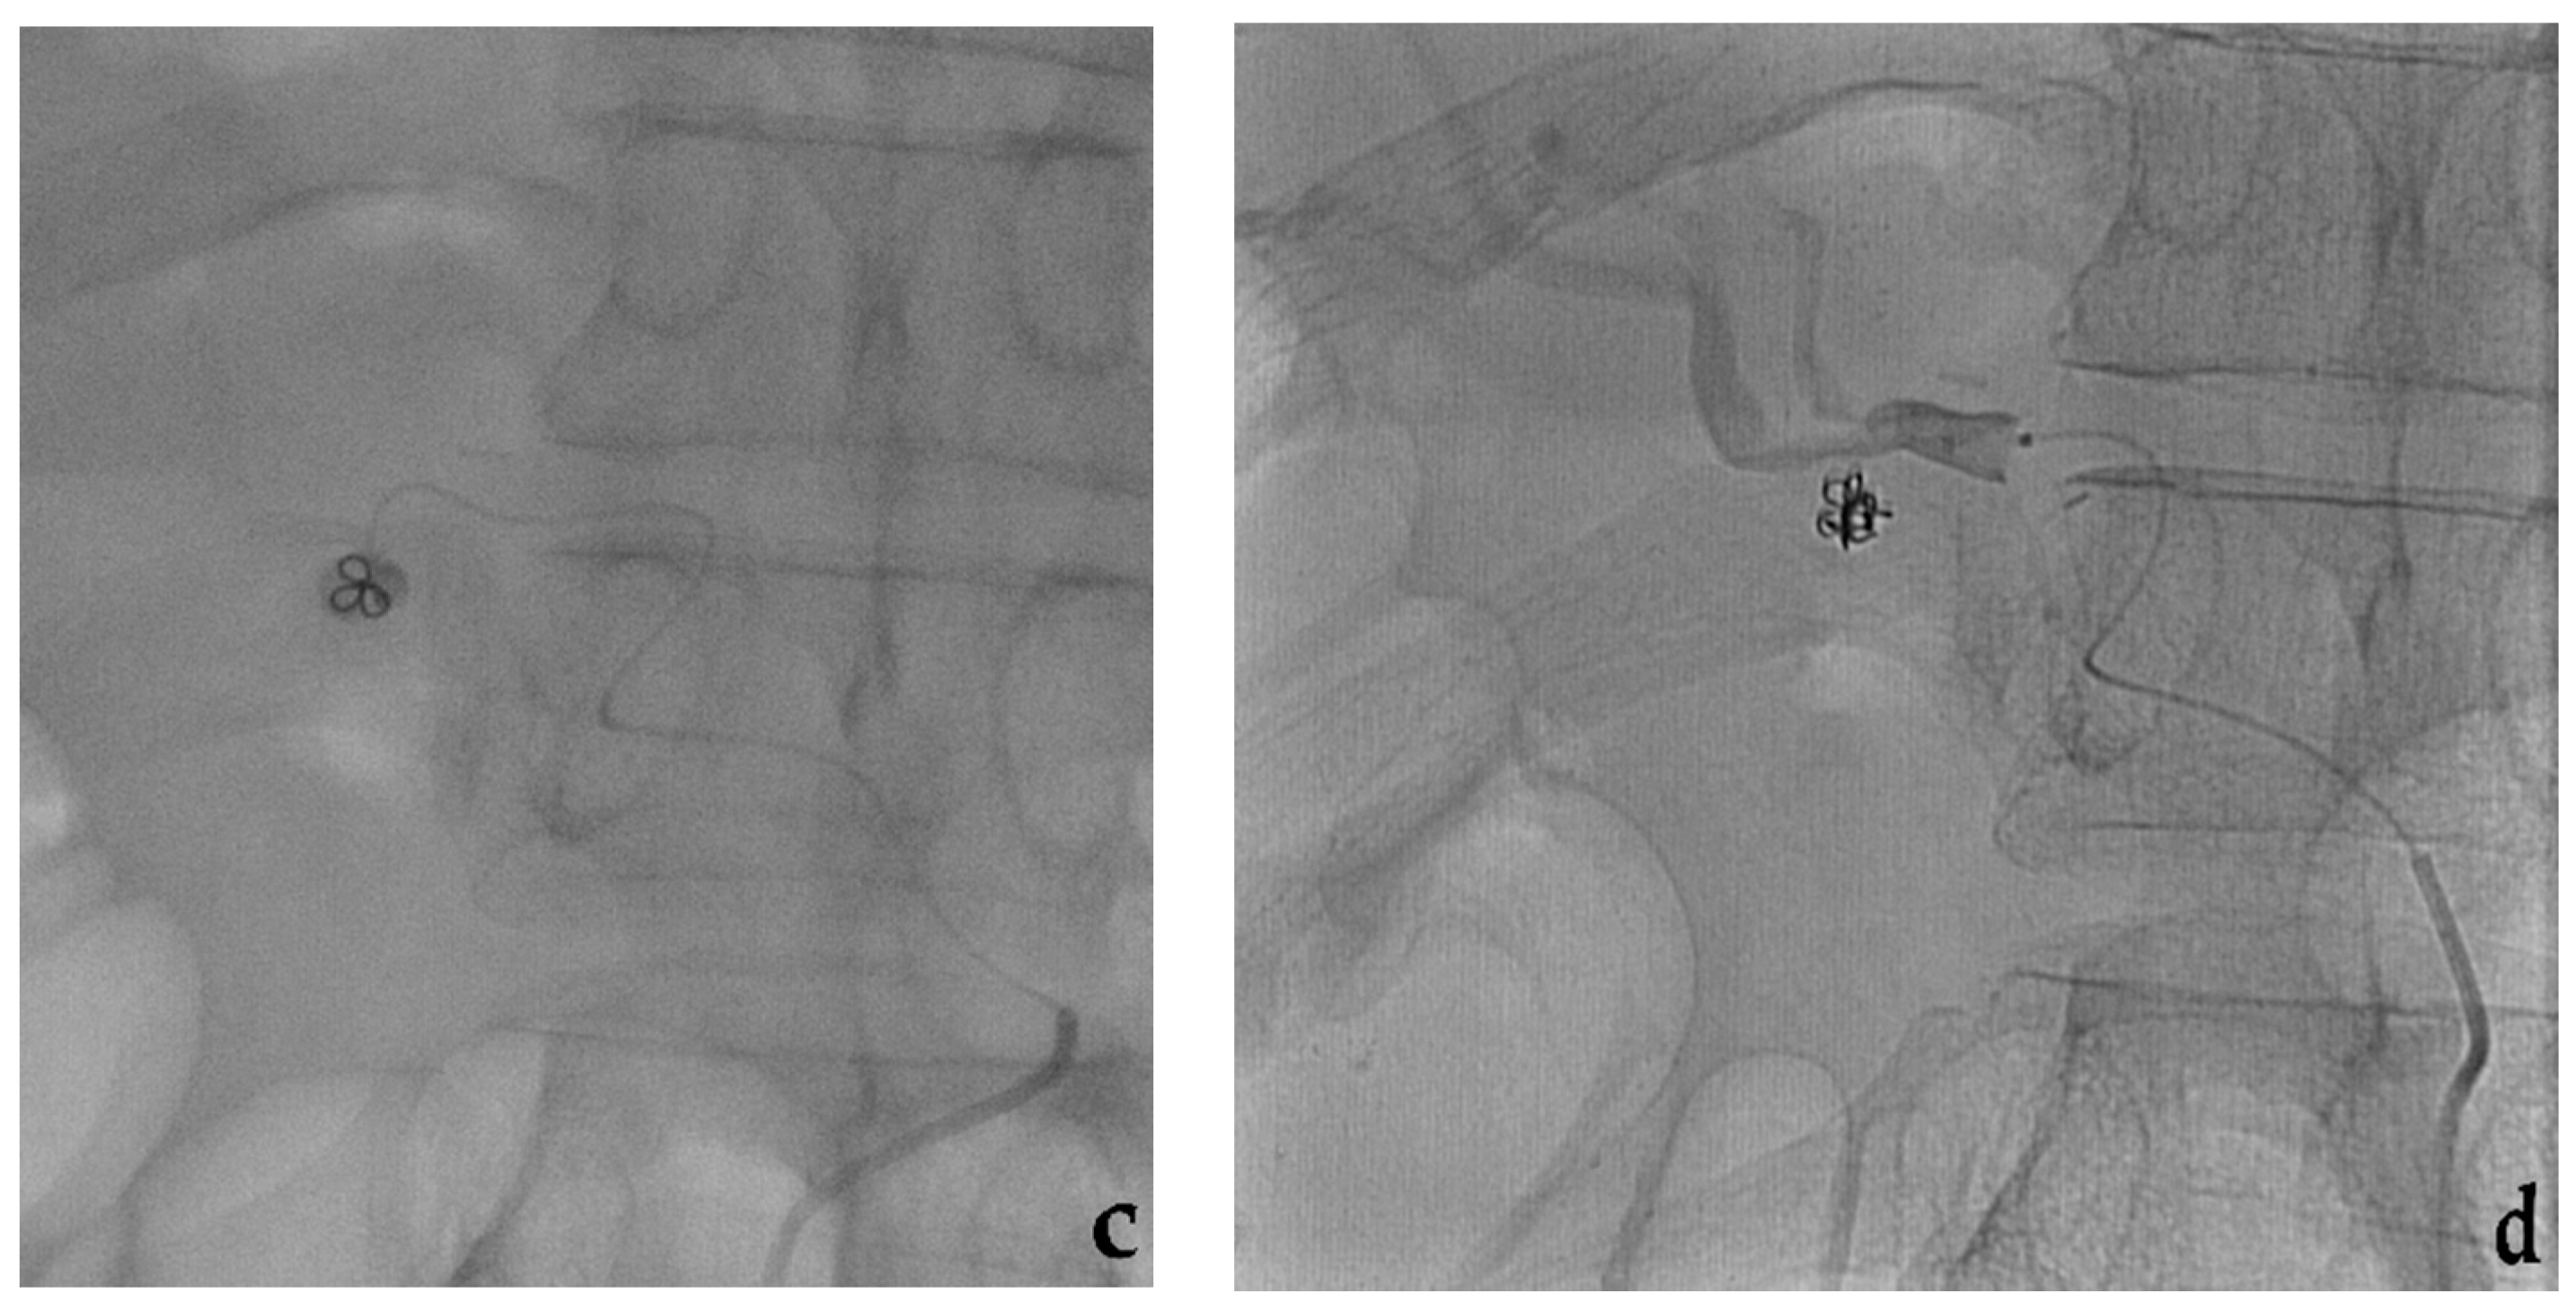

- Modestino, F.; Cappelli, A.; Mosconi, C.; Peta, G.; Bruno, A.; Vara, G.; De Benedictis, C.; Golfieri, R. Balloon-assisted coil embolization of a wide-necked aneurysm of the inferior pancraticoduodenal artery. CVIR Endovasc. 2020, 3, 62. [Google Scholar] [CrossRef] [PubMed]